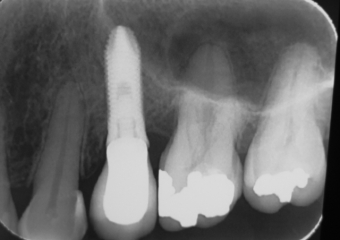

Imagens iniciais, observando a ausência do pré molar superior